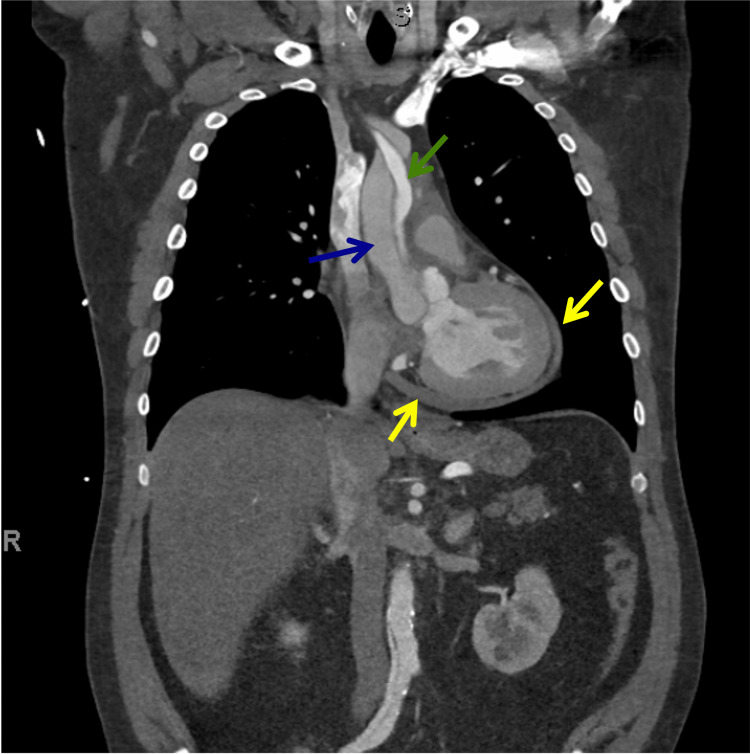

In view of chest pain associated with positive cardiac biomarkers, he was admitted to the Coronary Care Unit on intravenous nitroglycerin. While waiting for his admission, he suddenly had recurrent chest pain associated with marked hypotension (75/43 mmHg), for which the intravenous nitroglycerin was discontinued, fluid resuscitation was provided, and he was temporarily started on intravenous norepinephrine. The on-call cardiology team was contacted for an emergent evaluation. Subsequent ECG showed nonspecific ST-segment changes in leads V5-V6 (Figure 1). An emergent bedside echocardiogram revealed a moderate pericardial effusion of hemodynamic significance (Figure 2), as suggested by partial right ventricular chamber collapse (Figure 3) early in diastole and a plethoric non-collapsing inferior vena cava. The pericardial effusion also contained echogenic strands, which are highly concerning for blood clots. Additionally, a moderate to severe aortic valve insufficiency (Figure 4) was present according to color Doppler findings and pressure half-time assessment (315 ms). An intimal flap was visualized on the ascending and descending aorta, suggesting an extensive AD (Figures 2–6). A computer tomographic angiogram (CTA) of the chest and abdomen revealed a large pericardial effusion with an extensive AD extending from the level of the ascending aorta into his right brachiocephalic artery, the right and left common carotid arteries, and inferiorly to the right iliac artery (Figures 7–10), although not occlusive in diameter (or clinically). These findings were consistent with an extensive Stanford type-A AD with rupture into the pericardium, for which volume expansion and vasopressors were provided and emergently operated on the same day. The surgery included an open pericardiotomy with pericardial blood drainage, replacement of the ascending aorta from just above the commissure to the take-off of the innominate artery, partial replacement of the aortic arch, and aortic valve repair with successful results. Multiple intraoperative packed red blood cell units (8), fresh frozen plasma units (4), cryoprecipitate units (10), and platelet apheresis (3) were provided in view of bleeding complications related to the arrival provision of dual antiplatelet and anticoagulation therapy prior to the diagnosis of AD.